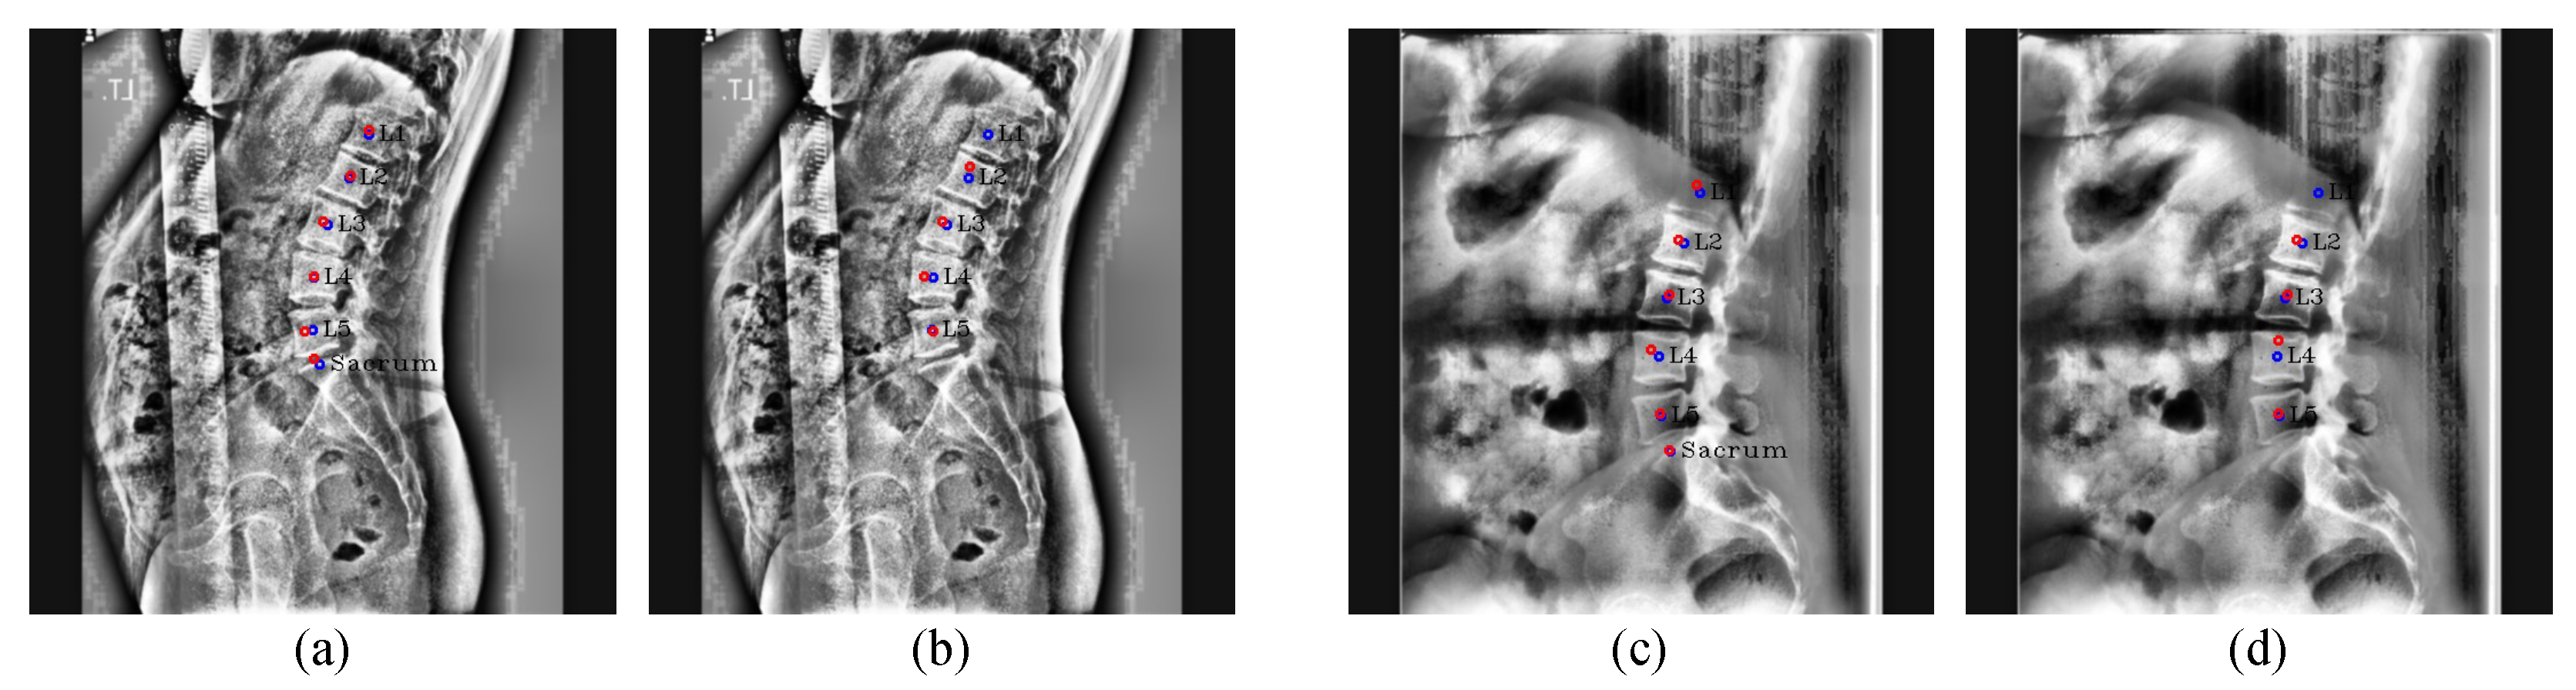

Figure 6. Post-processing results. (a,c) are the resulting images before performing post-processing, and (b,d) are the resulting images after performing post-processing on (a,c), respectively. The red circles denote the predicated centers of L1, L2, L3, L4, L5, and the sacrum in order from the top, and the blue circles and labels denote the ground truth of the center of each vertebra.

Post-processing: For Figure 5, when Pose-Net incorrectly predicts the center of the upper vertebra of L1 (T12) rather than L1 in a channel C 1 , where L1 should have been predicted, the successive target centers from C 2 to C 4 are also not properly detected. At this time, if we only selected the maximum point of each confidence map ( m a x 1 , m a x 2 , m a x 3 , m a x 4 , m a x 5 , m a x 6 ) as the center of each vertebra, there were cases where we would inaccurately extract the centers of some lumbar vertebrae, as shown in Figure 6a,c. To solve this problem, we used post-processing by taking advantage of the fact that all confidence maps for the centers of all lumbar vertebrae and the sacrum exist. First of all, we computed the distance d i = 1 , , 5 between the maximum points of each confidence map to determine whether C i = 1 , , 6 is the same case as Figure 6a,c. d i = 1 , , 5 is calculated as | | m a x ( C i ) , m a x ( C i + 1 ) | | 2 using the maximum points of C i and C i + 1 . Then, we calculated an average value m e a n ( d e x c e p t ( m a x ( d ) ) ) of the d i = 1 , , 5 , excluding the maximum value of d i = 1 , , 5 . If m a x ( d ) > m e a n ( d e x c e p t ( m a x ( d ) ) ) × 1.4, it was determined that part of the center coordinates of the vertebrae were not extracted exactly, and post-processing was carried out. Here, m e a n ( d e x c e p t ( m a x ( d ) ) ) × 1.4 was the maximum distance between two local maximum points of the center confidence map in our results.

The post-processing process is detailed in Algorithm 1 and Figure 7. In Algorithm 1, 0.4 in the equation p y > m a x ( C j + 1 ) 0.4 × d m a x was an experimentally obtained value, which can properly derive the center confidence map of the vertebra whose center was not extracted. As a result, thanks to the post-processing, we can remove the T12 center point from the improperly extracted center points and properly extract the unextracted center from the channelwise summed confidence map.